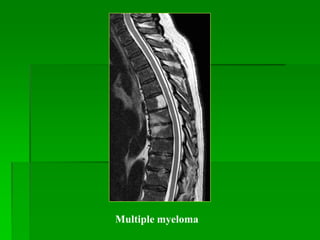

Plasmacytoma và Multiple myeloma

- Plasmacytoma là u đơn độc.

- Multiple myeloma là tổn thương đa ổ, thường gặp ở 50-60 tuổi và

thường gặp nhất ở cột sống (thân sống).

- MRI: tín hiệu thấp hơn tủy xương trên T1W, cao trên T2W. T2FS

giúp xác định độ lan rộng của tổn thương.

Plasmacytoma

MM

Multiple myeloma